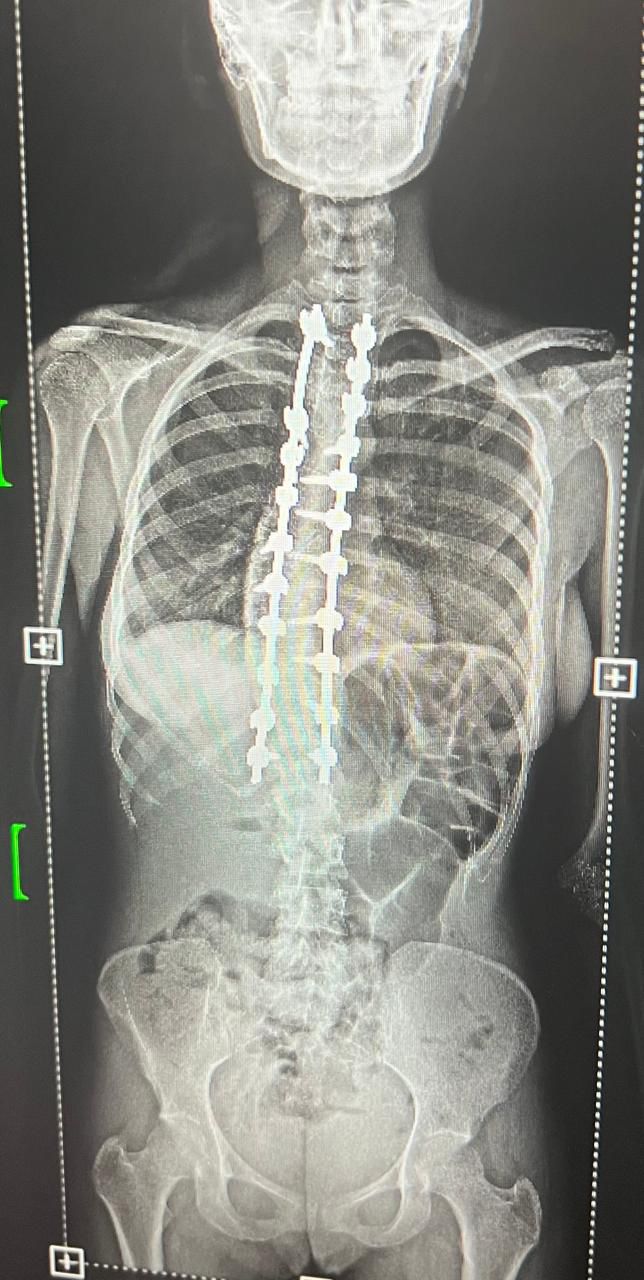

حقق قسم جراحة المخ والأعصاب والعمود الفقري بمستشفى القطيف المركزي أحد مكونات تجمع الشرقية الصحي إنجازا طبيا متقدما في مجال جراحة العمود الفقري، بعد نجاح أول حالتين لتصحيح انحناء العمود الفقري.

وجرى تشخيص الحالتين بعد تقييم طبي دقيق شمل الفحوصات الإكلينيكية والأشعة اللازمة، حيث تبين وجود درجات متقدمة من انحناء العمود الفقري استدعت التدخل الجراحي. وتم تنفيذ العمليتين باستخدام أحدث التقنيات الطبية، مع الاعتماد على أجهزة المراقبة العصبية لضمان أعلى مستويات الأمان أثناء الجراحة.

وتعد هذه العمليات من الإجراءات الجراحية الدقيقة والمعقدة، إذ تتطلب تنسيقا عاليا بين الفريق الجراحي والتخدير، إضافة إلى مراقبة عصبية مستمرة، وقد استغرقت كل عملية نحو ثمان ساعات.